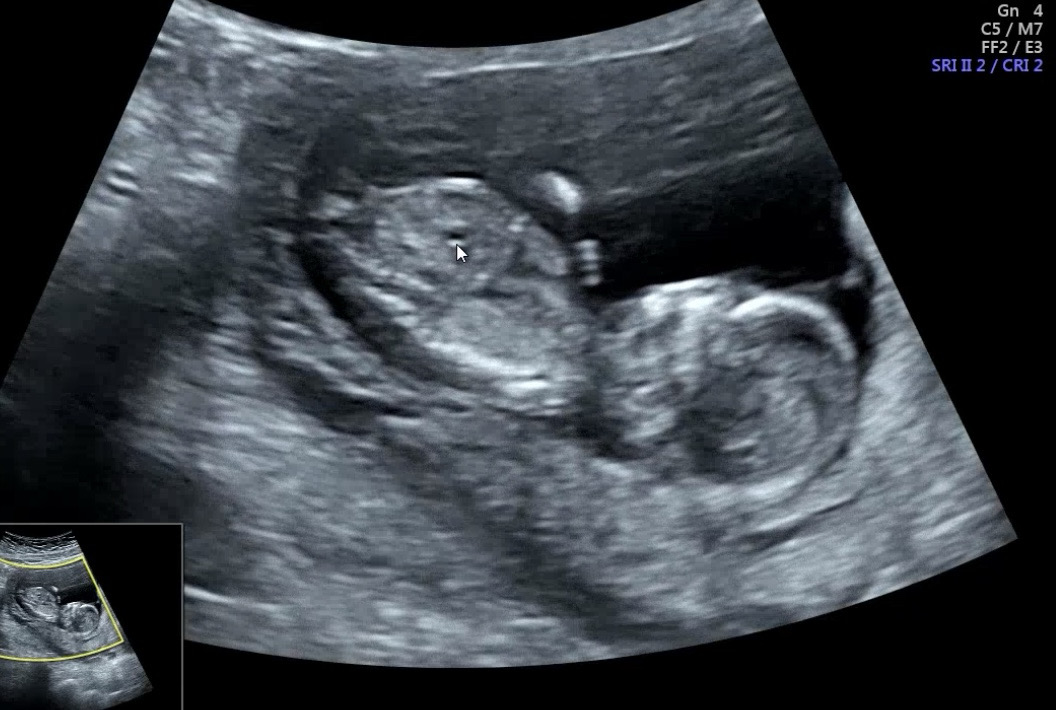

각도법 보일려나요..??

양반다리를 하고있어서 성별은 아직 모른다는데 이 각도에서도 보일려나요..?

다리로 가려져서 생식기 돌기가 안 보이네요.